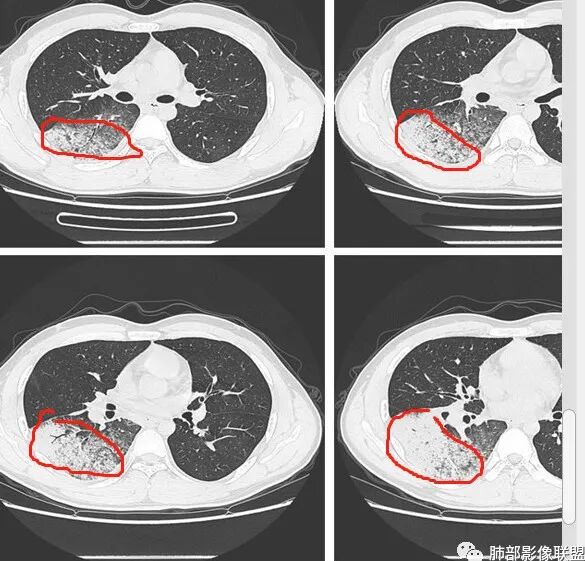

青年男性,急性病程,首次CT实变周围伴磨玻璃,边缘模糊,4天后病变明显进展大片状实变,边缘部可见磨玻璃影,内见支气管气象。考虑感染性病变,支原体?病毒?

初次右肺下叶斑片状磨玻璃及实变影,4天后复查明显进展,大片实变及磨玻璃,细网格,下叶近段支气管壁增厚,扩张,无胸腔积液,考虑社区获得性肺炎,病毒性肺炎?

青年男性,咳嗽咳痰发热4天,急性起病,抗感染治疗效果不佳,白细胞计数降低。第一次CT:右下叶斑片实变影伴磨玻璃影,边缘模糊。4天后复查CT:病变快速进展,右下叶大片实变影,内可见支气管充气征,边缘模糊,可见腺泡结节,叶间裂膨隆。考虑:大叶性感染,叶间裂膨隆,肺克?军团、病毒性肺炎无法除外。

患者青年男性,急性起病且使用抗菌素治疗后仍快速进展,主要症状表现为咳嗽、咳痰、畏寒、发热4天。血常规:白细胞及淋巴细胞降低。胸部CT:右下肺背段+基底段可见实变+GGO+支气管充气征,病灶位于胸膜外带下比靠近肺门处重,支气管壁未见增厚。诊断首先感染性疾病,腺病毒性肺炎可能性最大。

大家再看看周围的病灶,进展时细网格还是很明显吧

以小叶为单位向周围明显进展,累及间质尤其是小叶内间隔为主。

但是分布是胸膜下,周围重,内带轻。符合间质来源

这是一些散在分布的小叶内核心区域结节影。